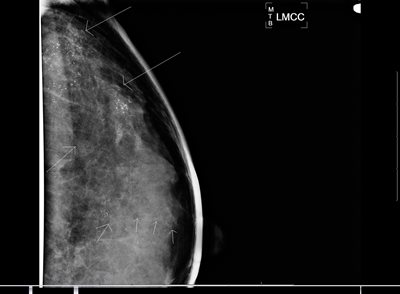

Analog screening mammography is a limited two-view examination of each breast, and is only advised for women who are completely asymptomatic. With digital mammography technology, the clarity of the images is superb, and the benefits of digital mammography are the greatest for younger women with dense breast tissue where analog examinations have limitations. (Figure 1) Mammography has the lowest radiation exposure of all radiographic examinations and even this amount is very tightly regulated by the Mammography Quality Standards Act, which is enforced by the Food and Drug Administration. Moreover, digital mammography results in a further decrease in radiation exposure to the glandular tissue by nearly 22% per view.16 These differences were not considered by the USPSTF when they emphasized the potential harm of screening mammography related to radiation exposure.

Figure 1a: Analog (film screen) right mediolateral oblique view (RMLO) on a patent with very dense breast parenchyma. The film screen mammogram was performed at an outside institution and provided to us as part of further workup and biopsy.

Figure 1b: Digital RMLO view on the same patient after a needle core biopsy and placement of clip in anterior right breast. Note the markedly improved tissue penetration, contrast, and better delineation of skin and subcutaneous tissues.